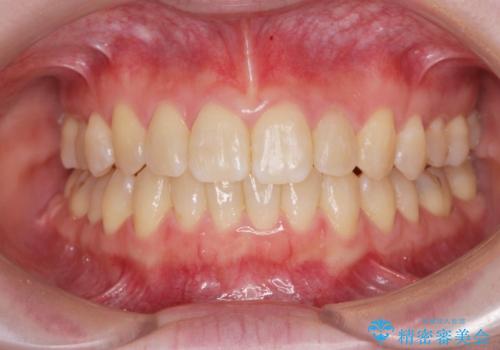

【ワイヤー矯正】八重歯 歯のでこぼこを治したい!